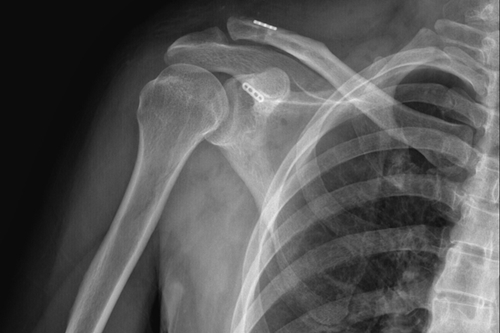

传统手术术后DR

骨三科主任朱述浪表示,近年来,随着生活水平的提高,患者对手术方式、手术效果的心理预期也不断提高。传统手术通过使用锁骨钩钢板来治疗肩锁关节脱位,其固定方式虽牢靠,但手术切口较大,术后极易出现脱钩、肩峰撞击,下骨溶解甚至造成骨折,疼痛发生率非常高,同时,内固定需2次手术拆除,且拆除后存在再脱位的可能。相比之下,带袢钢板内固定术能够有效恢复肩锁关节各方向的稳定性,不但符合肩锁关节生物学特性,还能最大程度地减少患者的创伤,并尽可能达到美容效果。该手术的开展,有望为广大患者提供更安全、更人性化的医疗服务。